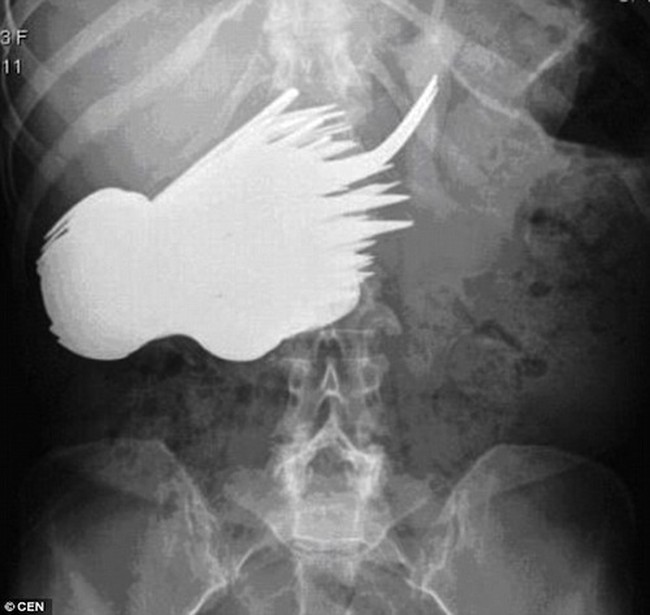

10 Penemuan Benda Aneh di Perut Manusia, Ada Paku hingga Ular

Sendok dan garpu jadi salah satu benda yang paling sering tertelan lewat tenggorokan. Tapi hasil pemeriksaan x-ray yang satu ini tunjukkan belasan sendok dan garpu yang berada di dalam perut manusia. Foto: Pool/Site

Jakarta - Sering disebut sebagai 'freak accident' atau kejadian aneh. Banyak benda hingga hewan yang tak sengaja berada di dalam perut manusia, seperti paku hingga ular.